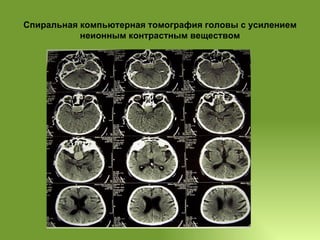

Спиральная компьютерная томографияголовы с усилением неионным контрастным веществом 26.09.2007 При СКТ определяется объёмное образование 45х37х32 мм однородной плотности (45-48 HU), располагающееся интра- суб- и супраселлярно, занимающее 1\3 основной пазухи, которое доходит до нижних отделов боковых желудочков, с ровными чёткими контурами. После введения контрастного вещества плотность образования не повысилась. III желудочек расширен до 10-11 мм, боковые желудочки также умеренно расширены, симметричны, срединные структуры мозга не смещены. Субарахноидальное пространство головного мозга равномерно расширено. Заключение: КТ-картина объёмного образования хиазмально-селлярной области, вероятнее всего- аденома гипофиза. Диффузные атрофические изменения ткани головного мозга.